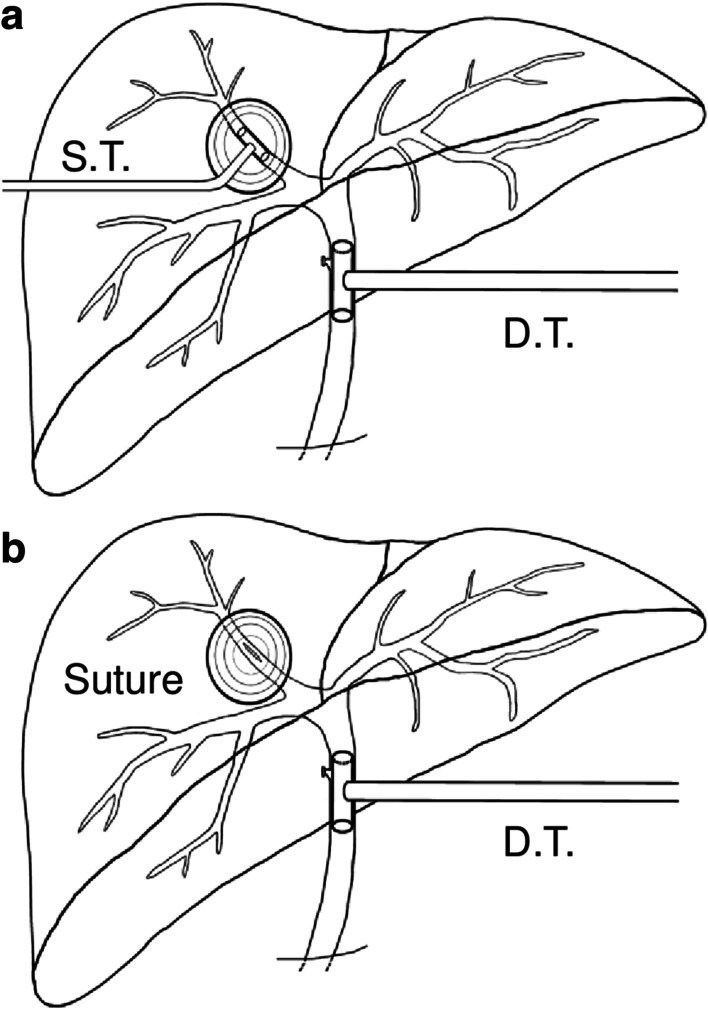

Double T-tube drainage

Schematic diagram (Fig. 4a) presented this procedure that was performed in 23 patients. In this method, main operation steps included: (i) PPC followed by exploration of inside surface of remnant peri-cyst to discover potential ruptured bile ducts; (ii) cholecystectomy, choledotomy and choledochoscopic exploration, removal of feces or debris in biliary tracts, biliary tree testing by infusing methylene blue through CBD, minor leakages in the residual cavity were sutured by using 4-0 or 5-0 absorbable sutures; (iii) upon exposuring FCBC site, one sustaining T-tube was placed where it ruptured, followed by a regular decompression T-tube at the CBD was introduced, thereafter, the rupture and the biliary tracs were reexamined by flushing methylene blue through decompression T-tube until no leakage was noticed; (iv) after careful examination and assuring patency of biliary tree, other two routine catheters were placed respectively at the residual cavity and the hepatic hilar region for post-surgical observation of any bile leakage or infections.

Single T-tube drainage with sutured fistula

Schematic diagram (Fig. 4b) showed this procedure that was performed in 28 patients. Main steps (i), (ii) and (iv) were same with above approach; (iii) the specific ruptured bile duct was sutured using 5-0 or 6-0 absorbable sutures, then a regular decompression T-tube at CBD was introduced, thereafter, reexamination by flushing methylene blue through T-tube was performed until no leakage was noticed.

Postoperative T-tube removal